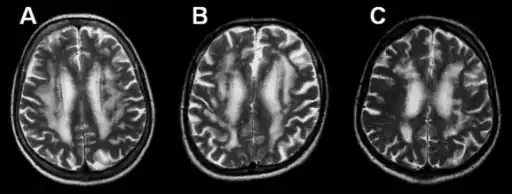

MRI-a-c)Three brains with the pure pathology of Binswanger's disease